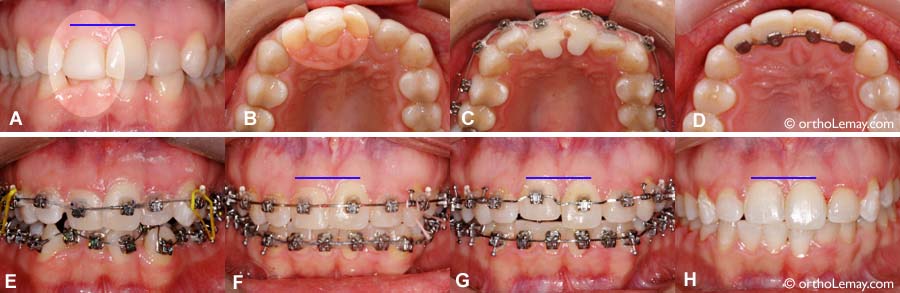

Camouflage d’une centrale qui est reculée, en rotation et plus courte que l’autre centrale.

(A et B) La centrale supérieure droite est reculée et en rotation. Elle est aussi plus courte (usure) que la centrale gauche et le niveau de gencive entre les centrales est inégal (ligne bleue). Vue occlusale (en plongée) une fois le composite enlevé et les appareils posés (du composite a été ajouté sur la surface intérieure des centrales). (D) Fin des corrections orthodontiques avec l’Attelle de rétention en place. (C et E) Pose des appareils correcteurs. (F) La centrale droite est avancée et détournée mais est toujours basse. (G) La centrale est remontée pour que le niveau de gencive soit égal entre les 2 centrales pour des raisons esthétiques. (H) À la fin du traitement, la centrale droite est plus courte et sera allongée à l’aide restauration qui sera faite par le dentiste généraliste.